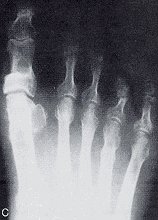

Figure 6

- The dorsoplantar view of an osteotomy site.

- The medial view of an osteotomy site.